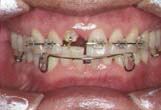

Forced eruption